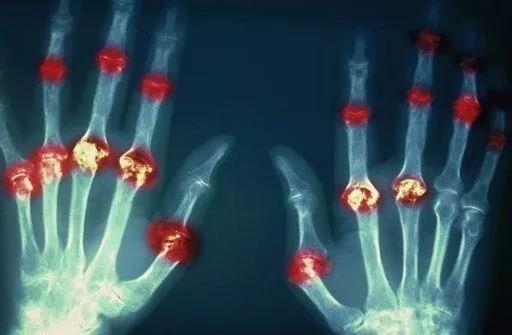

? 類(lèi)風(fēng)濕關(guān)節(jié)炎

類(lèi)風(fēng)濕關(guān)節(jié)炎是一種高度致殘的自身免疫性疾病,發(fā)病十年的患者中至少有50%的人失去勞動(dòng)能力。

類(lèi)風(fēng)濕關(guān)節(jié)炎©Health Same of Flickr

1977年,Baldwin在用骨髓干細(xì)胞移植治療再生障礙性貧血的過(guò)程中,意外發(fā)現(xiàn)患者的類(lèi)風(fēng)濕關(guān)節(jié)炎得到緩解。

2004年,歐洲骨髓移植和抗風(fēng)濕病聯(lián)盟對(duì)60例類(lèi)風(fēng)濕病關(guān)節(jié)炎移植患者進(jìn)行回顧性分析,這些患者的關(guān)節(jié)破壞都達(dá)到不可修復(fù)程度,生活不能自理,通過(guò)干細(xì)胞移植治療后,67%的患者得到明顯緩解。

我國(guó)國(guó)內(nèi)多家醫(yī)院已開(kāi)展了干細(xì)胞治療類(lèi)風(fēng)濕性關(guān)節(jié)炎的臨床研究。首例自體干細(xì)胞移植治療類(lèi)風(fēng)濕關(guān)節(jié)炎在北京協(xié)和醫(yī)院完成。經(jīng)過(guò)5個(gè)月隨訪(fǎng),這些經(jīng)常規(guī)藥物治療失敗且病情發(fā)展迅速的患者,在接受干細(xì)胞移植治療后,癥狀均獲得改善,關(guān)節(jié)腫脹消失,各項(xiàng)檢查指標(biāo)恢復(fù)正常。

解放軍323醫(yī)院2011年的一項(xiàng)臨床研究中,27位患者(對(duì)照組)只使用藥物治療;另外153位患者(細(xì)胞治療組)在藥物治療的基礎(chǔ)上進(jìn)行臍帶間充質(zhì)干細(xì)胞輸注。結(jié)果顯示,治療組DAS28、HAQ 評(píng)分、ACR20較對(duì)照組下降明顯(分值越低,療效越好),Th1/Th2趨于平衡、Treg升高與臨床實(shí)驗(yàn)指標(biāo)及癥狀的緩解直接相關(guān)。